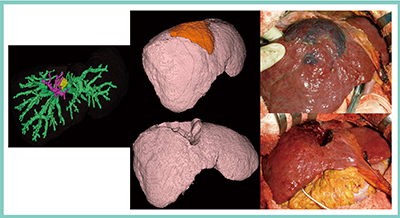

肝切除シミュレーションソフトウエアは,2004年に,当時・兵庫医科大学放射線科講師であった三浦行矣先生が,幕内雅敏先生(東京大学名誉教授/日本赤十字医療センター名誉院長/東和病院名誉院長)による肝臓の系統的区域切除術をコンピュータ上でシミュレーションすることをめざして,日立メディコ社(当時)との共同研究によって開発された。図1は,私が東京大学在職時の実際の症例であるが,肝前上区腹側枝(S8 vent)の染色範囲をシミュレーションして肝切除を行ったところ,切断面の画像が術中所見とほぼ一致している。現在では,画像処理ワークステーションを用いて肝容積評価や三次元画像を作成することが当たり前となっており,2012年には「画像等手術支援加算」が保険収載された。シミュレーションは,いまや「あると便利・安心」という位置づけになってきたと考える。

図1 初期の肝切除シミュレーションソフトウエアの症例